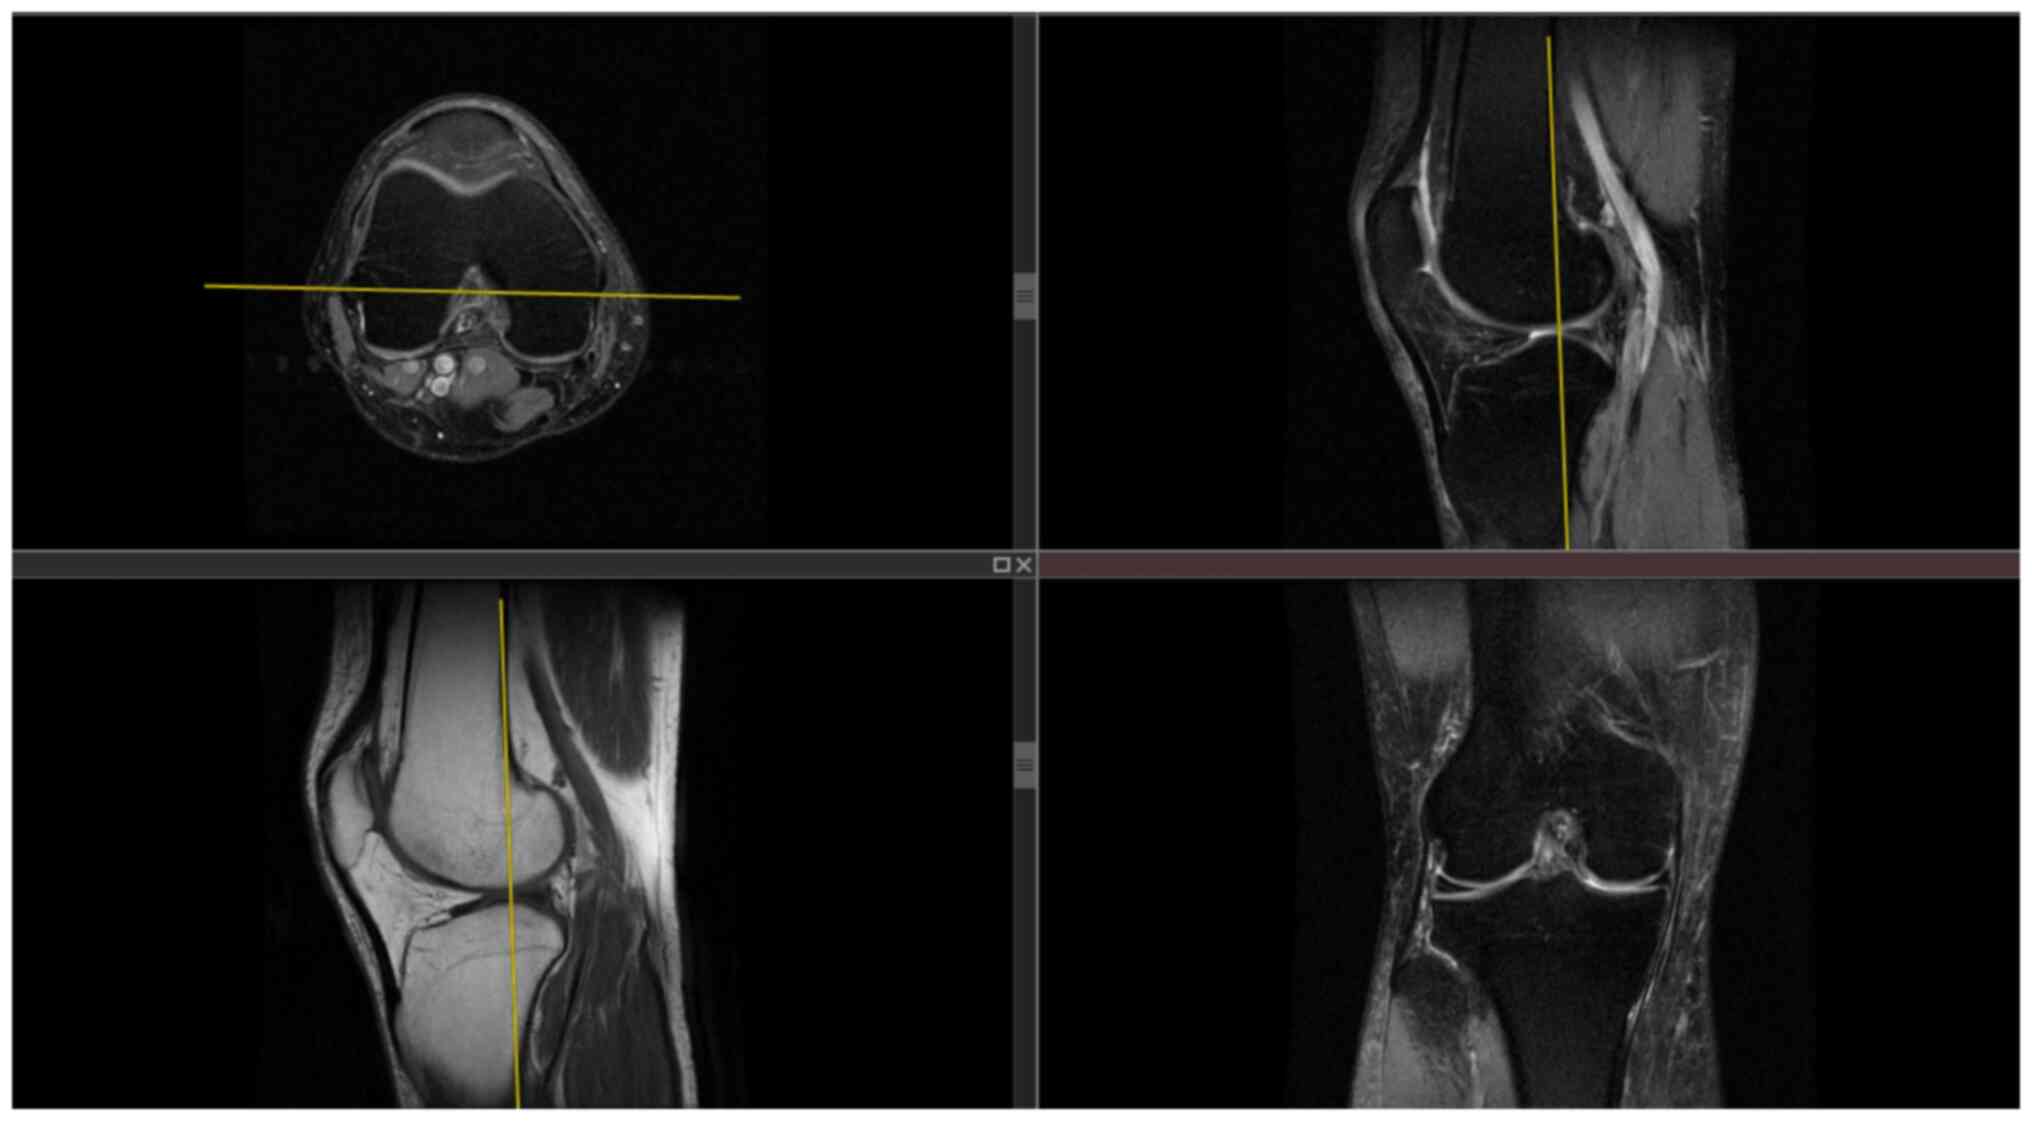

A flowchart of the FEA flow chart is revealed in Fig. 1. First, the Digital Imaging and Communications in Medicine file of the unilateral knee joint computed tomography (CT) and magnetic resonance imaging (MRI) scan data of a volunteer, 35 years-old male, 172.5 cm tall, and 69.4 kg in weight, was selected. The research protocol was reviewed and approved (approval no. CZEYYL2023016) by the Ethics Committee of Changzhi Second People's Hospital (Changzhi, China). The participant provided written informed consent before participating in the present study and underwent image scanning in October 2023 at the Second People's Hospital of Changzhi. CT images and MRI images are revealed in Figs. 2 and 3, respectively. The anteroposterior, lateral, double oblique and dynamic X-rays of the knee joint were selected, while bone deformities, fractures, tumors, infections and other diseases were excluded to obtain normal unilateral knee joint data. Mimics 21.0 software (Materialize, Inc.) was used to extract the data and reconstruct a normal knee joint STL model. In the Geomagic Studio 2014 software (Raindrop Geomagic, Inc.), the noise was repaired and reduced, surfaced, and three different geometric solid standard for the exchange of product (STP) models of the tibial platform pad posterior inclination corresponding to the unicondylar fixed platform prosthesis replacement of the knee joint were reversely processed. According to the UKA surgical protocol, the osteophytes on the medial femoral condyle and medial and lateral edges of the intercondylar notch were cleared and an osteotomy was performed precisely 2 mm below the lowest point of the tibial plateau. The femoral component was parallel to the long axis of the tibia in the coronal position and to the long axis of the femur in the sagittal position. The tibial component had posterior inclination angles of 3, 6 and 9˚ with the long axis of the tibia in the sagittal position. Taking the long axis of the tibia as an example, its determination method involves determining the midpoint of two lines connecting the anterior and posterior cortical bones distal to the knee joint line on the medial tibial platform (13,14). The LIDAKANG unicondylar fixed-platform prosthesis model was selected for matching according to the actual size parameters of the femur and tibia. The femoral condyle prosthesis and platform pad were made of M# (mid-sized prosthesis). During the model processing, the corresponding femoral and tibial bone ranges were first removed, and the prosthesis was correctly and reasonably installed according to the clinical surgical requirements. During the installation process, the posterior inclination angles of the tibial platform pad were set as 3, 6 and 9˚. Finally, a 1-mm thick bone cement layer was placed between the femoral condylar prosthesis and femur and between the platform support and tibia (15).

Figure 3

Magnetic resonance imaging image of the patient.